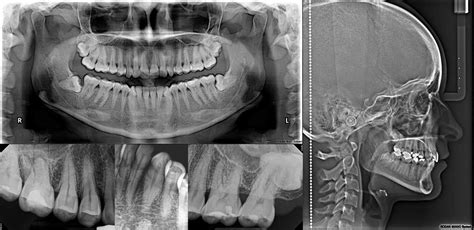

Radiografías extraorales

Las radiografías extraorales son técnicas de diagnóstico por imagen en odontología en las que el sensor o película radiográfica se coloca fuera de la boca del paciente. Es fundamental para los análisis cefalométricos que determinan la posición y alineación de los dientes, así como la relación entre los maxilares y el cráneo.